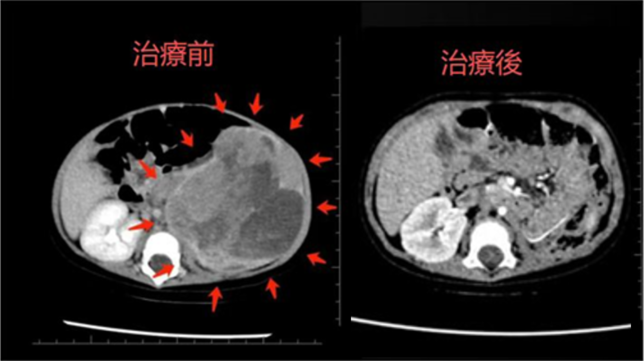

由于婴儿的生理特点,传统的放疗手段可能对正常组织,尤其是脏器,造成不可逆的损伤。因此,质子治疗成为了最佳选择。由清水翔星教授牵头,医院团队为患儿制定了个性化的质子治疗方案,利用质子束的独特“布拉格峰”特性,精准地将放射剂量集中于肿瘤靶区,最大限度减少对正常组织的伤害,尤其是在腹盆腔和脊柱区域的保护效果非常显著。

值得高兴的是,经过1年的随访,患儿无肿瘤复发,肾功能和肝功能持续保持在正常范围,进一步验证了质子治疗的长期安全性与疗效。这一结果不仅证明了治疗的有效性,也为质子治疗在高风险婴幼儿群体中的应用提供了更强的支持。